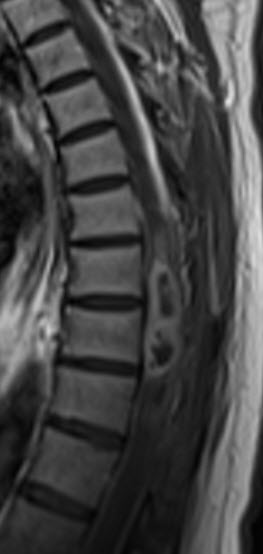

MRI of the dorsal spine with contrast and myelography and fibertraking and spectroscopy showing the recent lesions as seen in the below pictures with abscess formation.

MRI showing the new flare with abscess malformation and the old one

Fibertraking of the spinal cord at the lesion showing some scanty fibers ready for attack from behind (The middle picture)